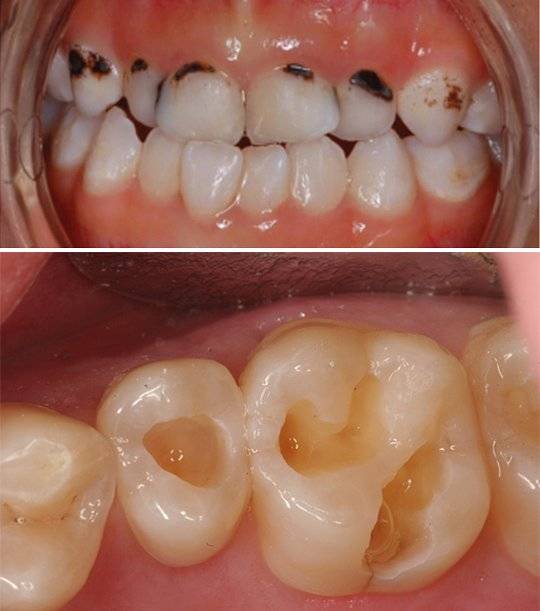

![심한 충치(위)와 충치를 치료한 후의 모습(아래). [사진 유원희]](https://img1.daumcdn.net/thumb/R658x0.q70/?fname=https://t1.daumcdn.net/news/201907/24/joongang/20190724101744139nqwp.jpg)

치과에서 가장 흔하게 보이는 양대 질환은 당연히 치주 질환과 치아우식증이다. 원인은 구강 내에 있는 미생물이 원활히 제거되지 않고 다른 음식물 찌꺼기와 결합해 발생하는 산이다. 바로 이 산이 치아조직에서 미네랄을 탈회해 치아 조직에 구멍을 낸다. 소위 ‘이가 썩는다’는 말로 종종 표현하지만 정확한 표현은 치아우식증이다. 초기 충치가 오래 방치돼 치아의 뿌리 부분인 치근단까지 녹여 생긴 농양이다. 아주 고약한 냄새를 풍기는 것이 이 병이다.

치관까지 근접하지 않으면 거의 자각증상이 없을 수도 있다. 치과 방사선 검사와 임상 검진으로 조기에 발견해 치료하는 것이 많은 고통과 번거로움을 피하는 지름길이다. 만약 상아질을 지나 더 깊이 있는 치수까지 퍼진 경우엔 차가운 물이나 뜨거운 물에 반응한다. 심지어 단 음식을 섭취할 때 자각 증상이 심하게 나타난다면 충치가 치아 조직에 깊숙이 침범한 상태다. 복잡한 신경치료로 충치로 손상을 입은 자연치아를 수복해야 한다.